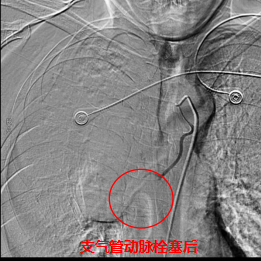

術中,數字減影血管造影(DSA)顯示患者右側支氣管動脈及胸廓內動脈增粗紊亂,末梢血管可見造影劑點狀外溢,明確為主要出血責任血管。團隊采用400?μm栓塞微球及560–710?μm明膠海綿顆粒,對出血動脈遠端實施精準栓塞,實現“末梢血管封堵”;同時,對肺動脈分支血栓相關區域也予以栓塞處理,以全面控制咯血來源。術后造影確認出血完全停止,患者安返病房后未再咯血,胸悶、氣促等癥狀顯著緩解。